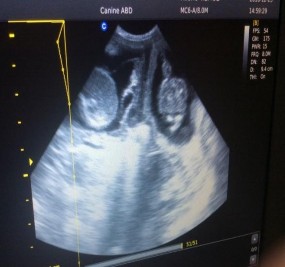

Nếu có chửa từ 28 ngày sau giao phối thì rất dễ chẩn đoán phân biệt với có chửa. Bởi khi có chửa, tim thai đập rất rõ thậm trí bọc nước ối cũng rõ và điển hình. Hình ảnh tử cung chứa thai hiển thị các bọc thai riêng rẽ, trong bọc có các khoảng tăng âm rõ là hình ảnh của thai, vùng trống âm bao bọc xung quanh là hình ảnh dịch ối, lớp màng ối của thai có cấu trúc bờ rõ ràng, hiển thị là những đoạn âm vang. Trên màn hình hiển thị có thể nhìn thấy cử động của thai và sự hoạt động của tim thai cho phép đánh giá sơ bộ tình trạng sức khỏe.

Còn đối với viêm tử cung thì trên màn hình hiển thị chủ yếu là những vùng trống âm thể hiện khối chất lỏng bất thường (dịch viêm) bên trong tử cung, đôi khi thấy xuất hiện một số vùng âm vang nhỏ rải rác. Kích thước vùng trống âm bên trong tử cung cho thấy khối lượng dịch viêm cũng như tình trạng viêm của mỗi cá thể, căn cứ vào đó bác sĩ thú y có thể đánh giá được tình trạng bệnh lý, đưa ra tiên lượng cũng như phác đồ điều trị thích hợp cho từng ca bệnh. Trong bệnh viêm tử cung (viêm dạng kín), lòng tử cung tích nhiều dịch.

Viêm tử cung dạng đóng là dễ dàng được xác định bởi sự hiện diện của sự căng phồng, các bọc chứa đầy chất lỏng ở sừng tử cung có thể chiếm một diện tích lớn trong xoang bụng và dễ dàng hình dung nếu đầu dò đặt bất cứ nơi nào trên thành bụng. Độ dày của thành tử cung có thể thay đổi tùy theo về mức độ căng phồng và chất chứa bên trong. Sừng tử cung căng phồng có thể dễ dàng theo dõi bên ngoài mép của bàng quang và xác định trong phạm vi khối ruột.

Siêu âm rất nhạy để xác định ngay cả sự tích tụ chất lỏng nhỏ trong lòng tử cung vào giai đoạn đầu của bệnh. Trong trường hợp này, dịch trong lòng tử cung được xác định tốt nhất ở vùng cuối của sừng tử cung và thân tử cung.

Hình 3.2. Hình ảnh siêu âm viêm tử cung |